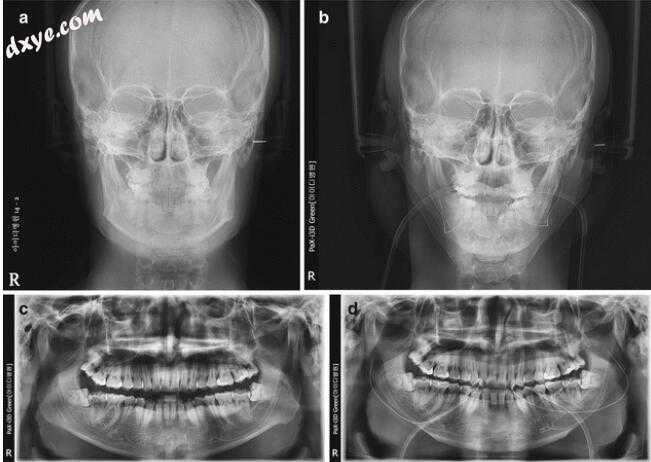

图6.4病例的放射学检查结果1.前(左)和术后(右)头颅图和全景图

图6.6病例2的放射学检查结果:术前(左)和术后(右)头颅图和平板图